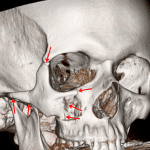

- Acute right zygomaticomaxillary complex fracture with nondisplaced fracture of the zygomatic arch, mildly displaced fractures of the zygomatic and frontal bones near the zygomaticofrontal suture, mildly displaced fractures of the lateral and inferior orbital walls, and mildly displaced fractures of the anterior, posterior, and medial walls of the maxillary sinus. The orbital floor fracture involves the infraorbital foramen

- ZMC fracture

Acute right zygomaticomaxillary complex (ZMC) fracture with nondisplaced fracture of the zygomatic arch, mildly displaced fractures of the zygomatic and frontal bones near the zygomaticofrontal suture, mildly displaced fractures of the lateral and inferior orbital walls, and mildly displaced fractures of the anterior, posterior, and medial walls of the maxillary sinus. The orbital floor fracture involves the infraorbital foramen.